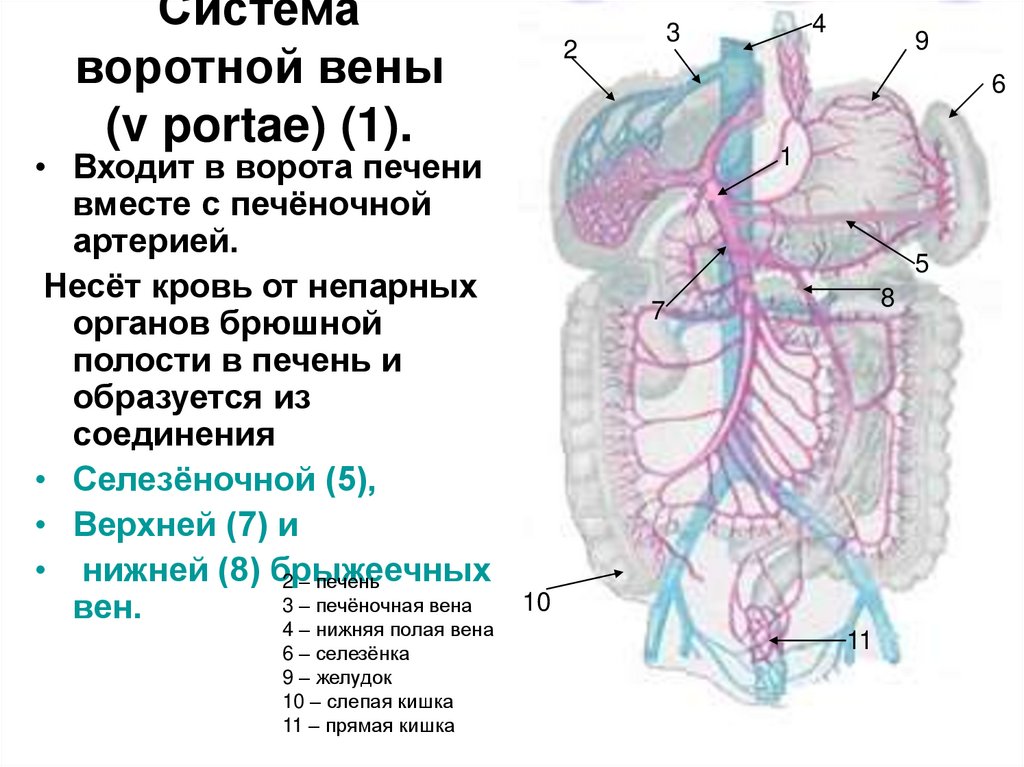

Особенности и диагностика левостороннего кровотока